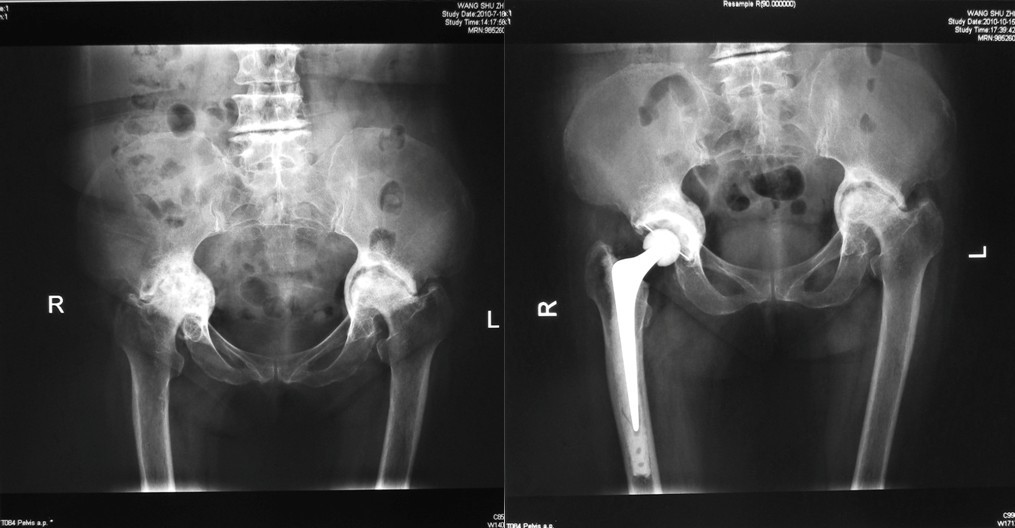

⑵Ⅱ型缺损:类风湿性关节炎合并髋臼内陷,髋臼缘完好。行颗粒骨打压植骨,三代骨水泥技术髋关节置换。

患者髋关节Harris评分由术前的平均35.8分提高到术后的平均81.3分,平均随访4-6月,植骨愈合良好, X线片上一例出现透亮带,无症状予继续观察,未行再次翻修,没有发生伤口或深部感染。无坐骨神经麻痹和髋关节脱位发生。